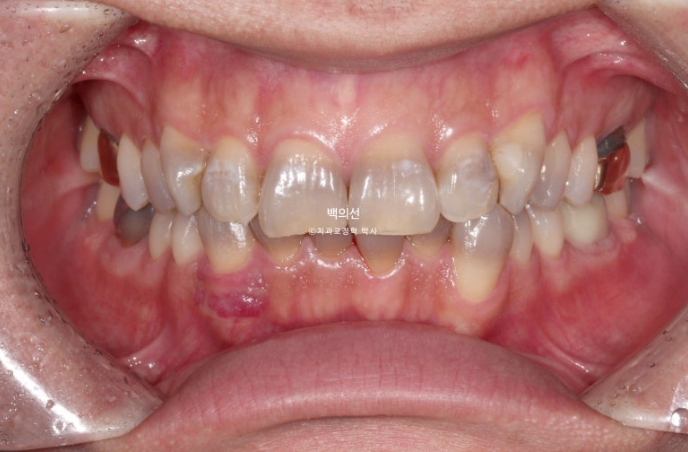

This patient came in for no-prep laminate treatment in December 2023.

They wanted all teeth, from the canines back to the premolars, both upper 8 and lower 8, covered with laminate.

The discoloration is severe, with a fairly deep gray tone.

However, as you can see from the front, the canine crowding means laminate treatment would be difficult unless orthodontic treatment is done first.

In the lower front teeth, there are varying heights in addition to the canine crowding.